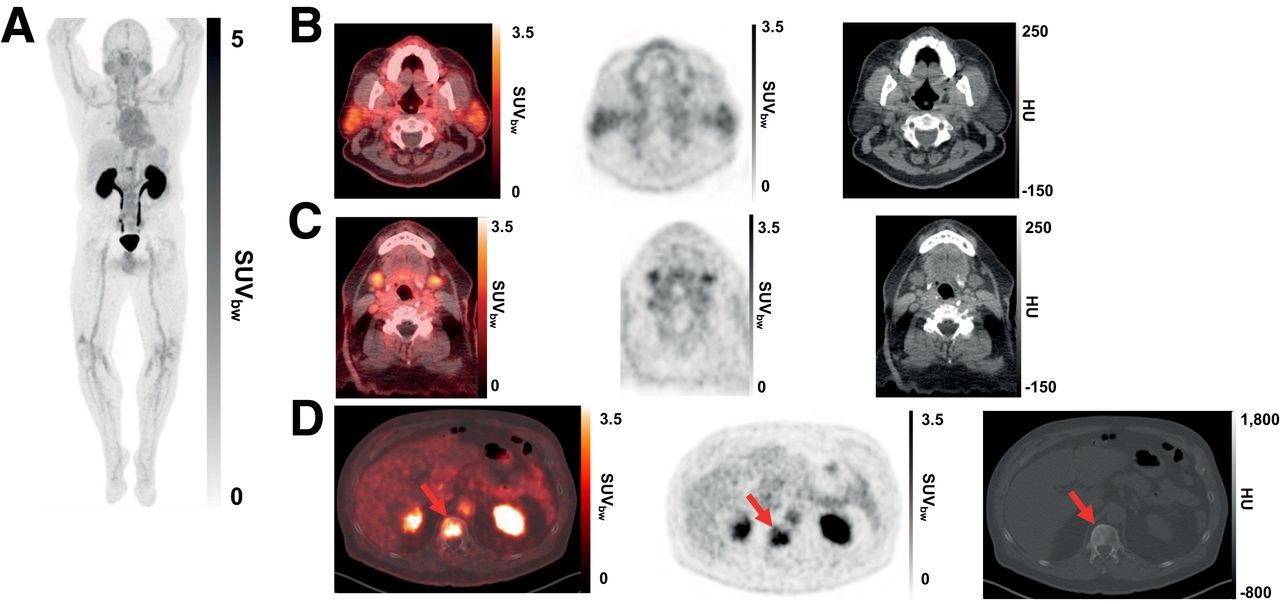

Пэт псма что это

Пэт псма что это 104 фотографий